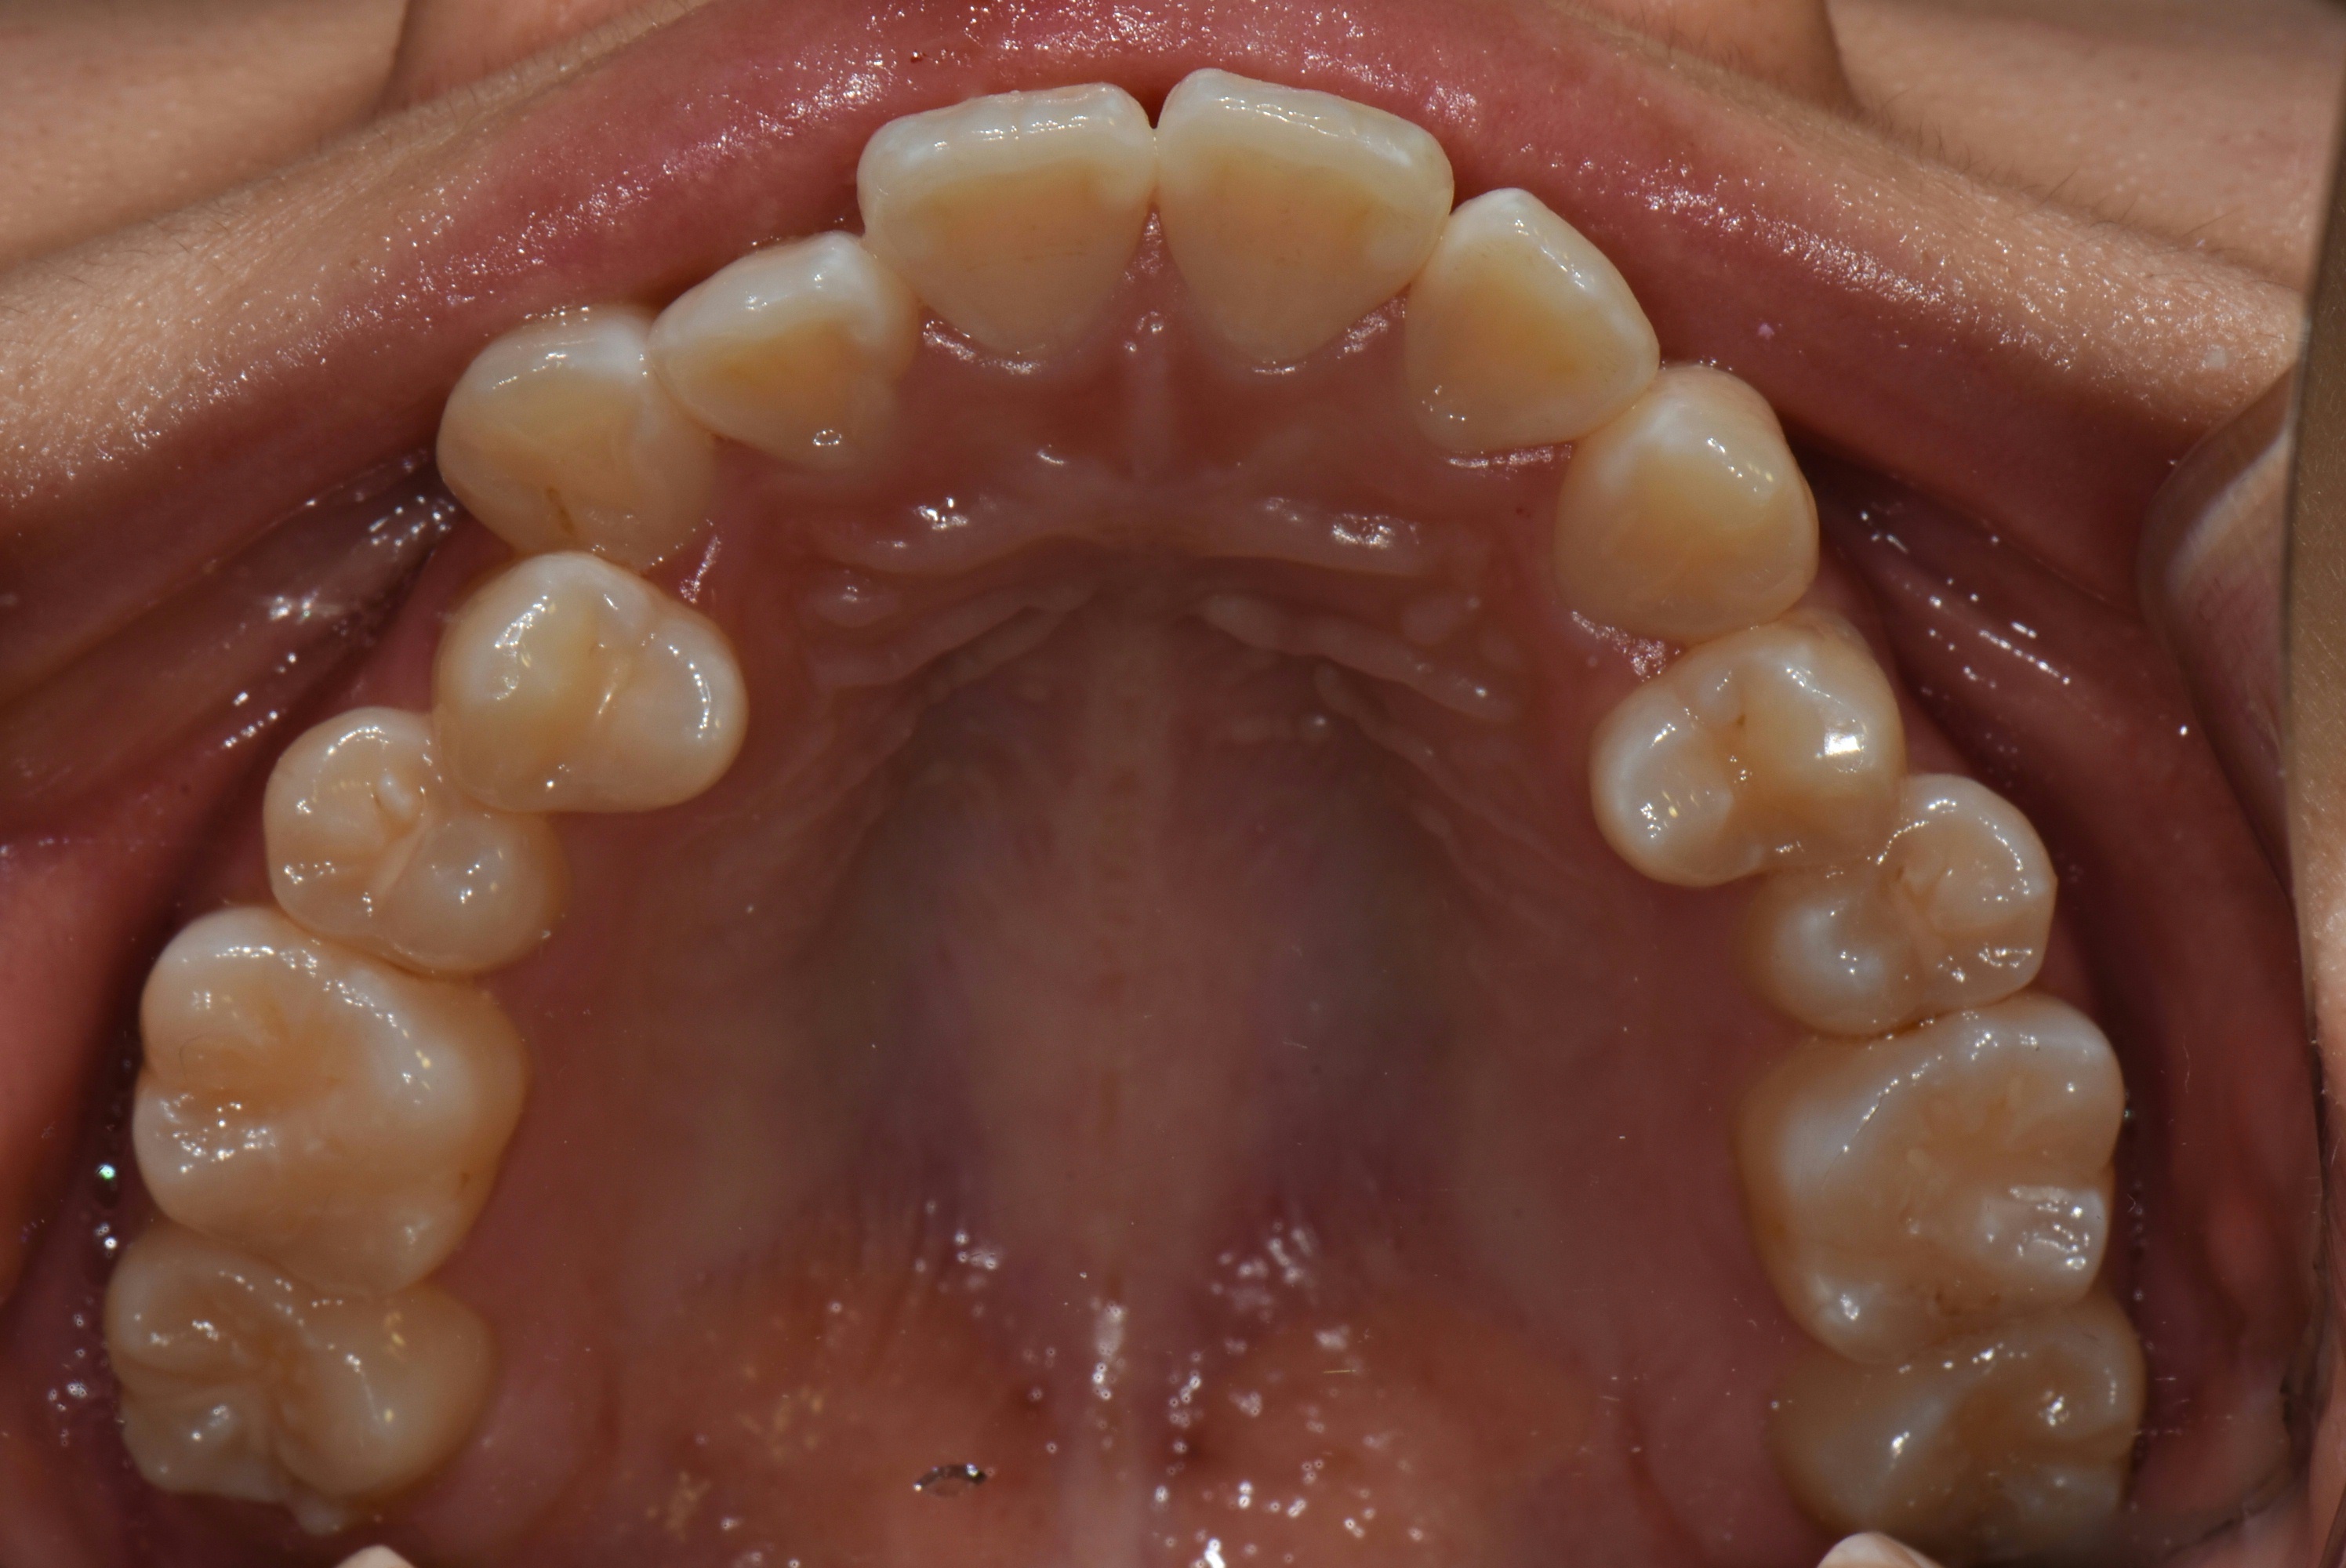

치료 전 사진입니다.